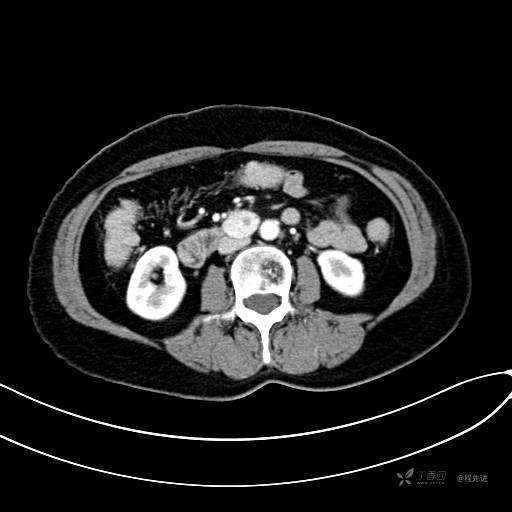

CT增强静脉期